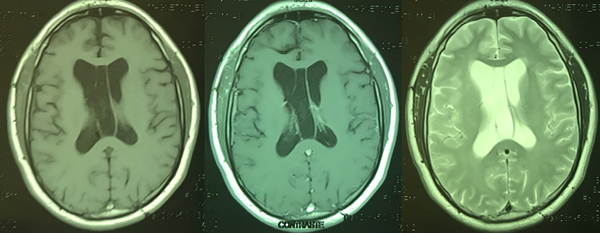

Un hombre de 45 años de edad con antecedentes de asma, consultó al servicio de urgencias por cefalea holocraneana de intensidad 9/10 en la escala numérica análoga, de tipo opresiva que mejoraba parcialmente con analgésicos, asociada a alteración en la marcha. Al examen físico neurológico presentaba una paresia leve en el miembro inferior derecho. Se realizó una resonancia magnética (RM) de cerebro la cual evidenció una gran lesión a nivel del cuerpo del ventrículo lateral derecho de 7 x 6 x 7 cm que sobrepasaba la línea media y se extendía al III ventrículo. Tras la administración de contraste se evidenció un leve realce heterogéneo. Así mismo se evidenció una leve dilatación ventricular (Figura 1).

Figura 1: resonancia magnética de cerebro que evidencia una lesión heterogénea a nivel del ventrículo lateral derecho con extensión al III ventrículo y desplazamiento de línea media, la cual realza luego la administración de contraste.